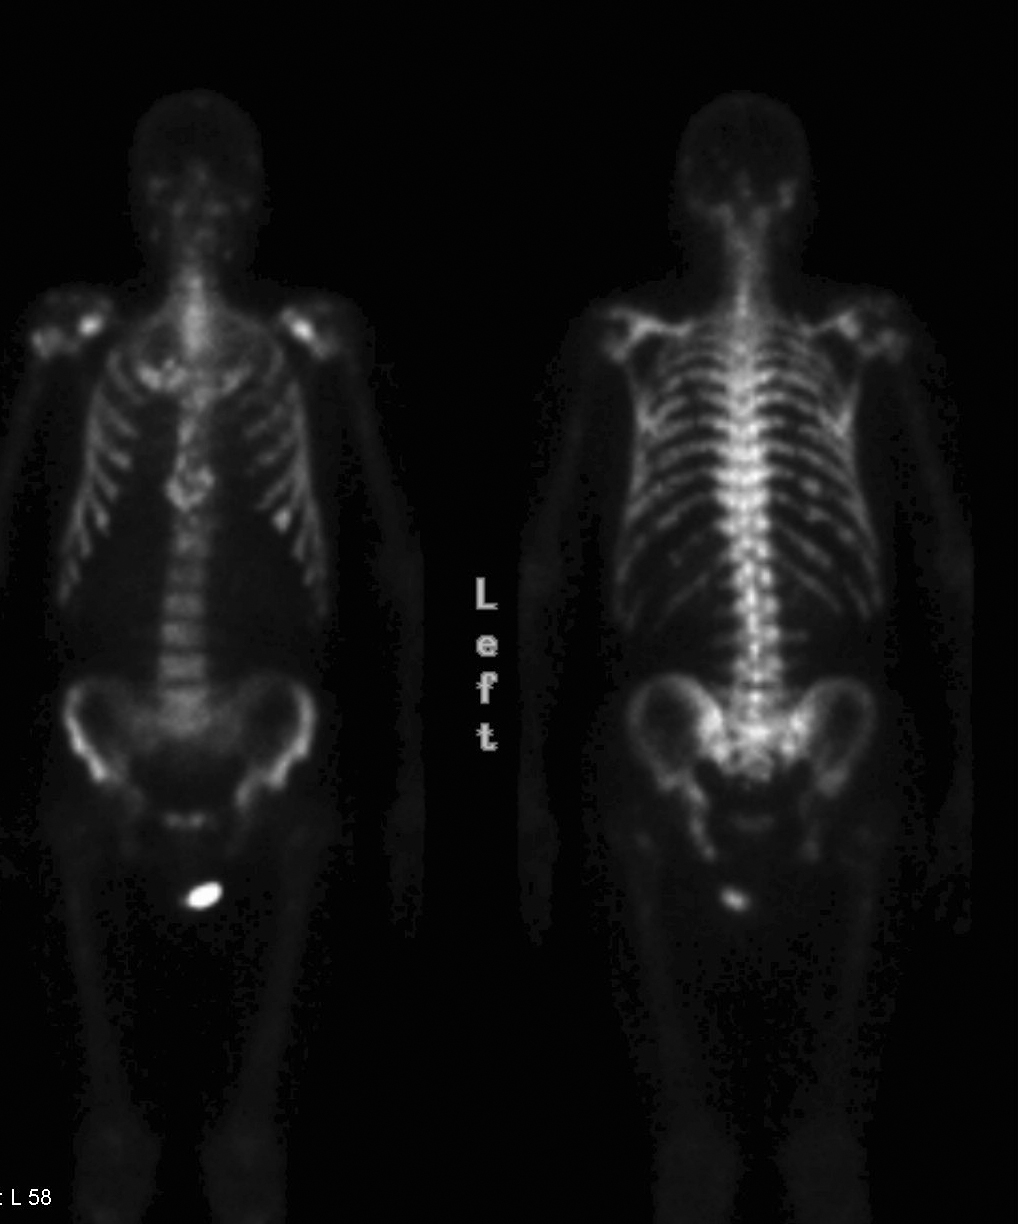

Prostate Bøne scan